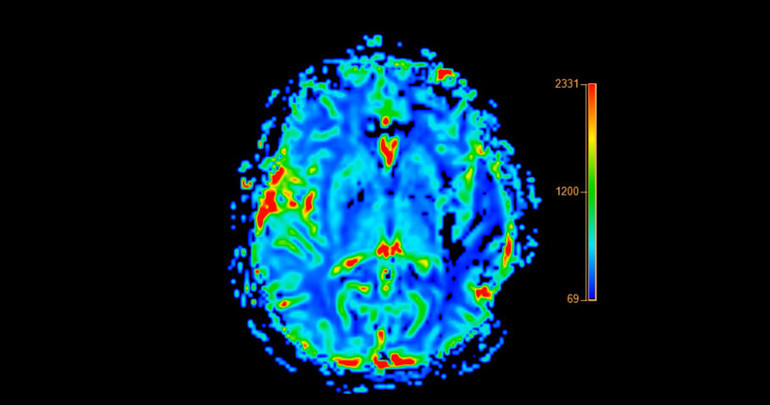

Alzheimer, beyinde iki proteinin anormal birikimi ile karakterizedir; semptomlar ortaya çıkmadan en az 20 yıl önce kümelenmeye başlayan amiloid ve amiloid biriktikten sonra düğümler oluşturan tau. Tau, bilişsel gerileme ile çok daha fazla ilişkilidir.

Washington Üniversitesi'nde nörolog olan Dr. Jorge Llibre-Guerra, “Whitney'nin beyni amiloid ile dolu, muhtemelen ailesindeki diğer mutasyon taşıyıcılarından bile daha fazla, çünkü bu kadar uzun yaşadı. Ancak çok az tau'su var. Tau birikimine ve tau yayılmasına dirençli. Esnekliği burada yatıyor” dedi.